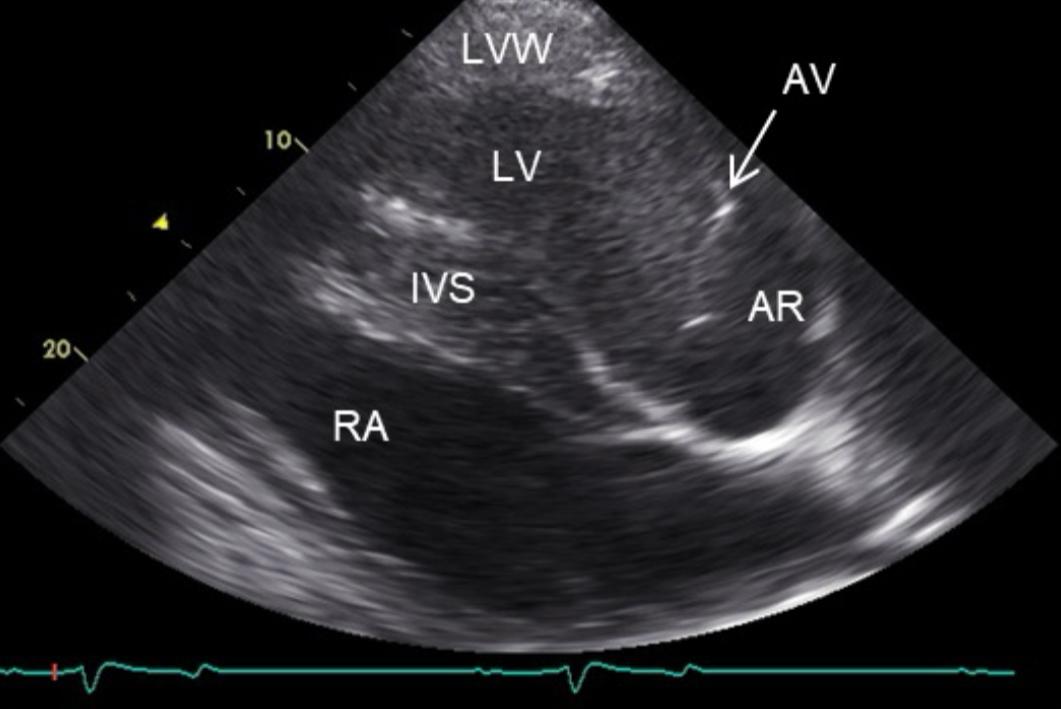

- Darstellung des Herzens (in verschiedenen Ebenen) und des Blutflusses

- nicht vollständig schließende Aortenklappe sichtbar

- pathologische Verwirbelungen des Blutflusses

- nach Messung Vergrößerung der linken Herzkammer

Diagnose: hochgradie Aortenklappeninsuffizienz, mittelgradige Vergrößerung linker Ventrikel (sekundär)

- „undichter“ Verschluss der Aortenklappe, Rückfluss von Blut aus Aorta in die linke Herzkammer